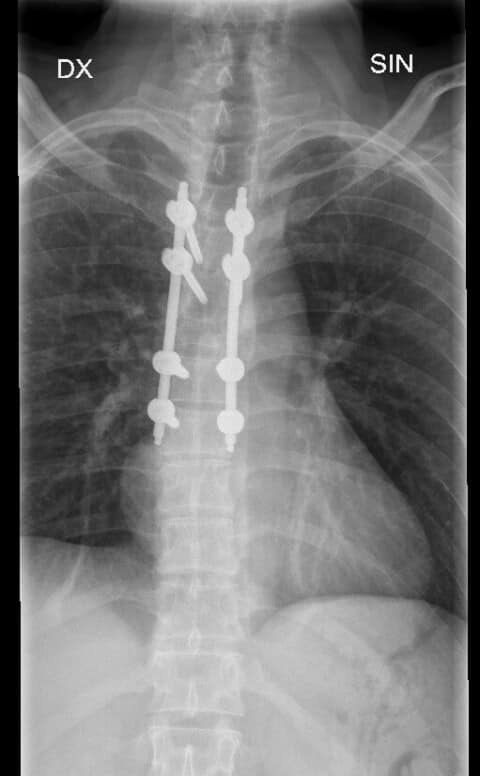

1. Mugurkaula krūšu daļas lūzuma stabilizācija perkutāni mazinvazīvi t.i. stabilizējošās skrūves un stieņi tika implantēti caur atsevišķiem maziem griezieniem, nevis plaši atverot brūci. 2. Mugurkaula otrā kakla skriemeļa stabilizācija ar speciālu pielāgotu kompresijas skrūvi.

Mazinvazīvā metode, kad operācija pacientam tiek veikta caur vairākiem nelieliem griezieniem, TOS tiek praktizēta jau daudzus gadus, tomēr šāda veida operācija, kad vienam pacientam tiek vienlaicīgi maztraumatiski izoperēts un nofiksēts gan mugurkaula kakla daļas skriemeļa lūzums, gan mugurkaula krūšu daļas nestabils lūzums, ir notikusi Latvijā pirmo reizi, stāsta TOS.